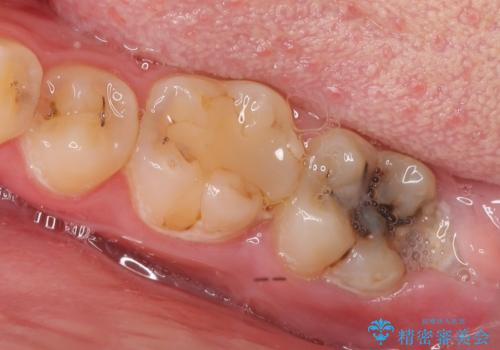

一番奥歯の後ろに虫歯が 処置の難しい虫歯

セラミックインレー 下の一番奥歯 歯ぐきの厚みを減らしてぴったりに入れます(ディスタルウェッジ+骨外科)